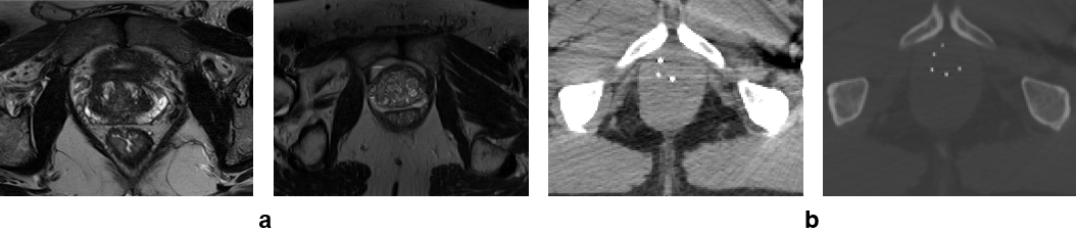

Automatic segmentation of anatomical structures in medical images has various medical applications. For example, in radiotherapy prostate segmentation is essential in the diagnosis, therapy, and post-therapy analysis of prostate cancer. It is critical in selecting patients for a specific treatment, to guide source delivery and in computing dose distribution [1, 2]. T2-weighted MRI is the modality of choice for prostate segmentation. However, CT and US are also routinely used because: 1) CT image is used to calculate the dose distribution due to its characteristics of relating the density of tissues with the voxel intensity, and 2) US imaging is suitable for real-time image guided radiotherapy. Despite the need for accurate segmentation of the prostate in radiotherapy, manual segmentation is subjective to inter and intra-observer variabilities, time-consuming, and depends on the experience of the physician. Automatic and reliable segmentation of the prostate on these images is thus an important but difficult task due to the inhomogeneous and inconsistent contrast of prostate boundary and large shape variations. This is particularly complicated on CT images because of the inherent low-contrast imaging characteristics of CT for soft tissues (such as prostate boundary) as can be seen from Fig. 1 (b).

Refer to caption

Figure 1: Prostate image examples showing image contrast variations in: (a) T2-weighted MRI, and (b) CT images with seeds from low-dose-rate brachytherapy.